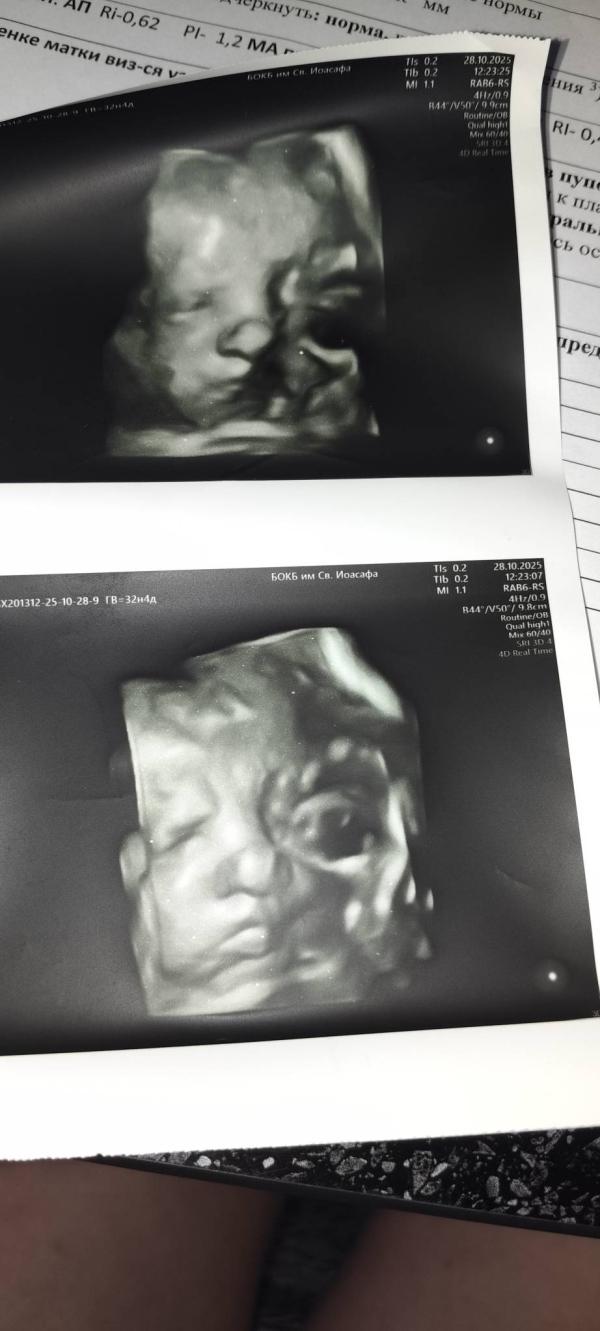

Всё третий скрининг пройден ,ура!!!

Моя Бусинка весит 2 кг 💖 врач сказала мало 😟

По месячным было: 32 недели 1 день

По узи: 32 недели 3 дня

Вес: 2044